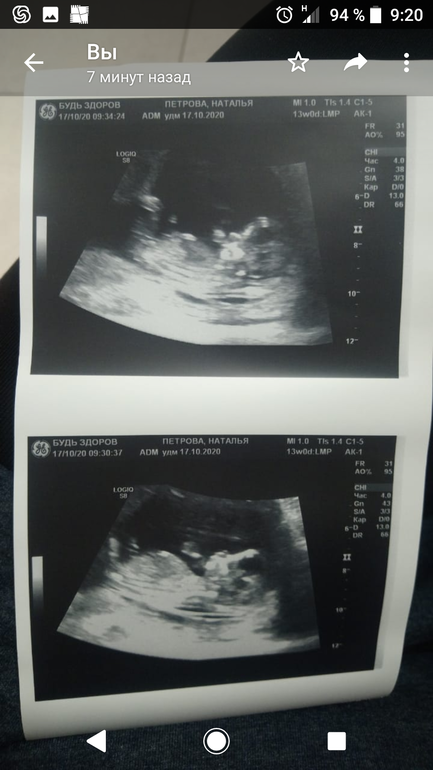

Натали в Благополучная беременность 5 лет Девчули, гляньте пол кто разбирается Пол малыша Пожааалуйста, может можно определить. 13 нед ровно Посмотрите еще 20 записей на эту тему Отменить Ответить Мечты сбываются Вы не подтверждали пол? 29.10.2020 Ответить Мечты сбываются Думаю девочка 21.10.2020 Ответить Евгения Девочка 17.10.2020 Ответить Натали Нет ещё, завтра пойду, может покажет 29.10.2020 Ответить Гермиона Это всё "вилами по воде", на таком сроке даже специалисты ошибаются. 17.10.2020 Ответить Anya я за мальчика,если правильно вижу бугорок 17.10.2020 Ответить Таня А я за парня, но если уж совсем откровенно, то фото неудачное, поэтому просто порадусь за вас и за здорового малышастика 17.10.2020 Ответить Натали Спасибо, недельки через 2 схожу, может чего отвиснет там 17.10.2020 Ответить Катя А более четкого кадра нет? 17.10.2020 Ответить Натали Нет вот, все что есть( 17.10.2020 Ответить Катя Просто далековато и размыто! Но если то что я вижу бугорок, то скорее всего девочка 🙏 17.10.2020 Ответить Натали Спасибо. Врач тоже сказала девочка, но не точно как обычно 17.10.2020 Ответить Женя Если это половой бугорок, то похоже на девочку)) 17.10.2020 Ответить Натали ) спасибо 17.10.2020 Ответить 1 скрининг Гендерпати🤰❤️ Чаты Беременных Выберите чат: Январята-2026 Февралята-2026 Мартята-2026 Апрелята-2026 Майчата-2026 Июнята-2026 Июлята-2026 Августята-2026